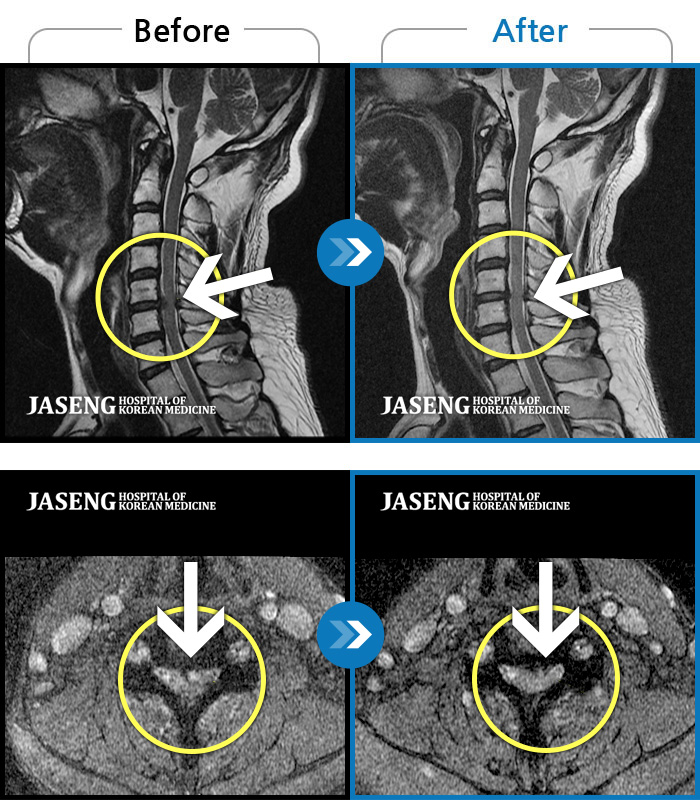

허리디스크

분당 · 진은석 원장

교통사고로 인해 기존의 퇴행성 디스크가 파열되어 극심한 경추의 통증과 손의 힘 빠짐, 손가락의 저림 증상을 호소하였음

촬영시기

2024.04.20 ~ 2024.11.02

2024.11.15

조회수 555